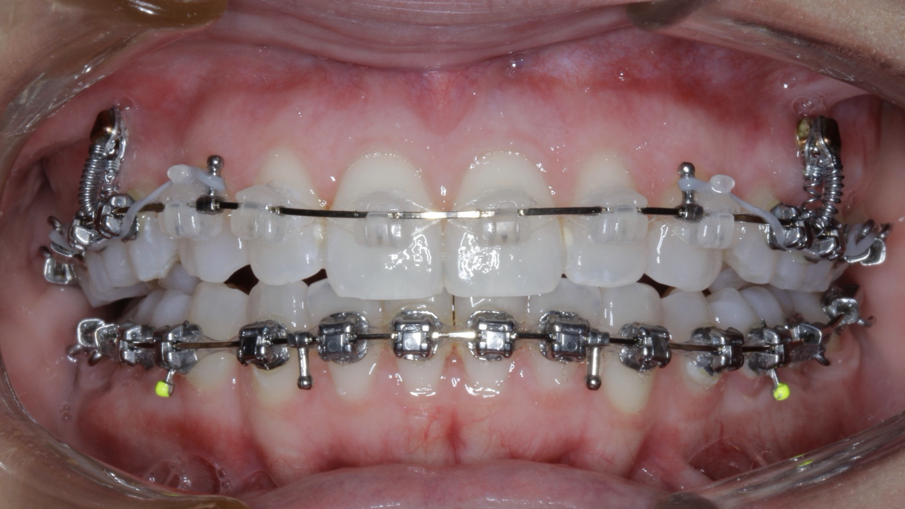

Case 5: Skeletal expansion

In cases where absolute maxillary expansion is desired with little to no dental side effects, maxillary anchorage with TADs is a wonderful solution. This allows for sutural expansion that has little to no dental compensation. Many designs exist for TAD placement with expansion. In some cases, a tissue-borne expander is used with no anchorage on the molars. This is typically used to encourage the maximum amount of skeletal expansion when dental tipping is undesired (Figs. 52 & 53). In cases where molar anchorage is desired, a banded approach can be used in conjunction with TADs (Figs. 54–59).

Fig. 54

Fig. 55

Fig. 56

Fig. 57

Fig. 58

Fig. 59